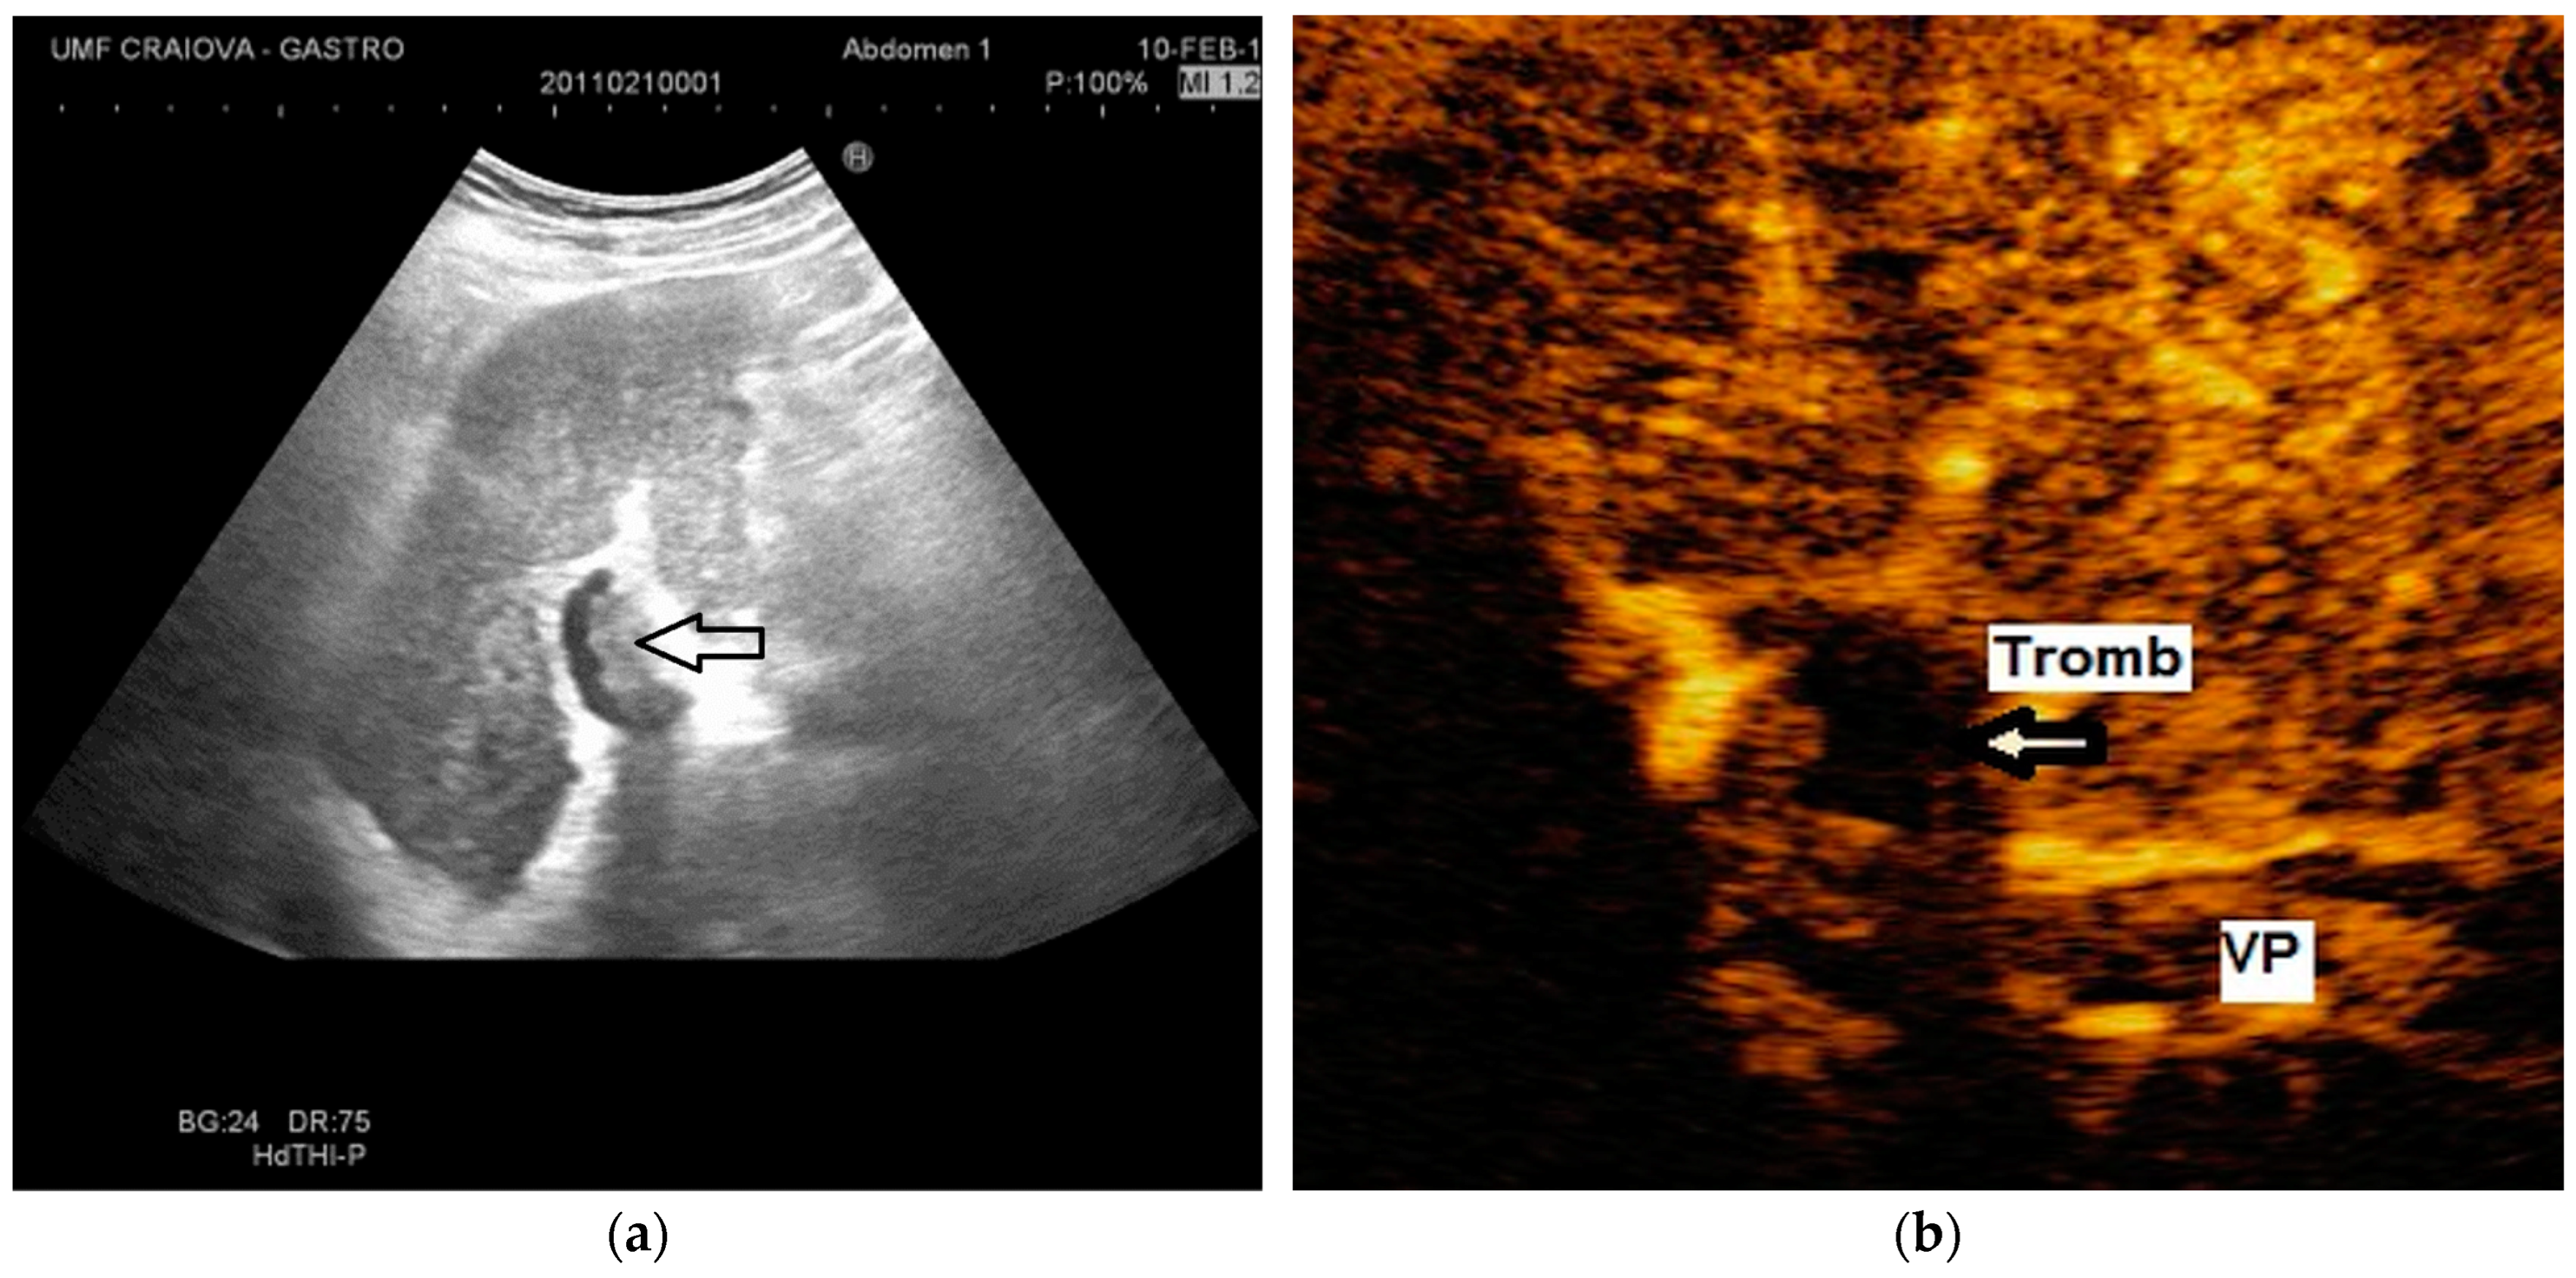

The diagnosis of PVT and PC is made by imaging procedures (transabdominal ultrasound with a Doppler or contrast-enhancing computed tomography scan, magnetic resonance imaging, or angiography in the case of therapeutic intended procedures) [1,3,12,13,14,21,29]. Transabdominal ultrasound is a reliable procedure in 60–100% of cases, with an anechoic aspect in recent cases (requiring Doppler examination or CEUS) and a hypoechoic or hyperechoic aspect in chronic cases [22,29]. Doppler examination may show an anechoic or hypoechoic thrombus and a slower (<15 cm/sec) or absent portal blood flow, and is considered the gold standard (color Doppler) for the diagnosis of PC [1], with a sensitivity and specificity of 95% (Figure 1 and Figure 2) [22]. CEUS can help the diagnosis of benign or malignant PVT, can characterize associated focal liver lesions [30], allows a better characterization of PVT [31], and also permits better detection of PC—Figure 3 and Figure 4 [32]. CT scan and MRI (Figure 5 and Figure 6) are more accurate for the evaluation of liver causes (HCC, abscesses, and other tumors) or other local causes (pancreatitis, diverticulitis, and appendicitis), and for complications (bowel infarction or perforation), and may show permeability of the portal venous system and the flow direction [1,22]. Malignant PVT has intra-thrombus arterial signals on CT, MRI, and/or CEUS, with portal vein diameter frequently 23 mm or above, and with the presence of the tumor at imaging examination (Figure 4 and Figure 6) [21].

Figure 1.

Portal cavernomatous transformation. (a) Multiple serpiginous echo-free structures (vessels) replacing the normal portal vein are seen in B-mode at the hepatic hilum; (b) Color Doppler examination confirms the presence of venous flow within the vessels of the cavernoma.

Transabdominal ultrasound with Doppler protocol (Figure 1a,b and Figure 2a,b), CT scan (Figure 3a,b), and MRI (Figure 4a,b) were used for the diagnosis in 88.9, 75.1, and 15% of cases, respectively. CEUS was used for the diagnosis in 49 cases (25.9%) but in only 29 cases was it used for the evaluation of the thrombus, and in two cases for cavernoma diagnosis (Figure 5a,b and Figure 6a,b).